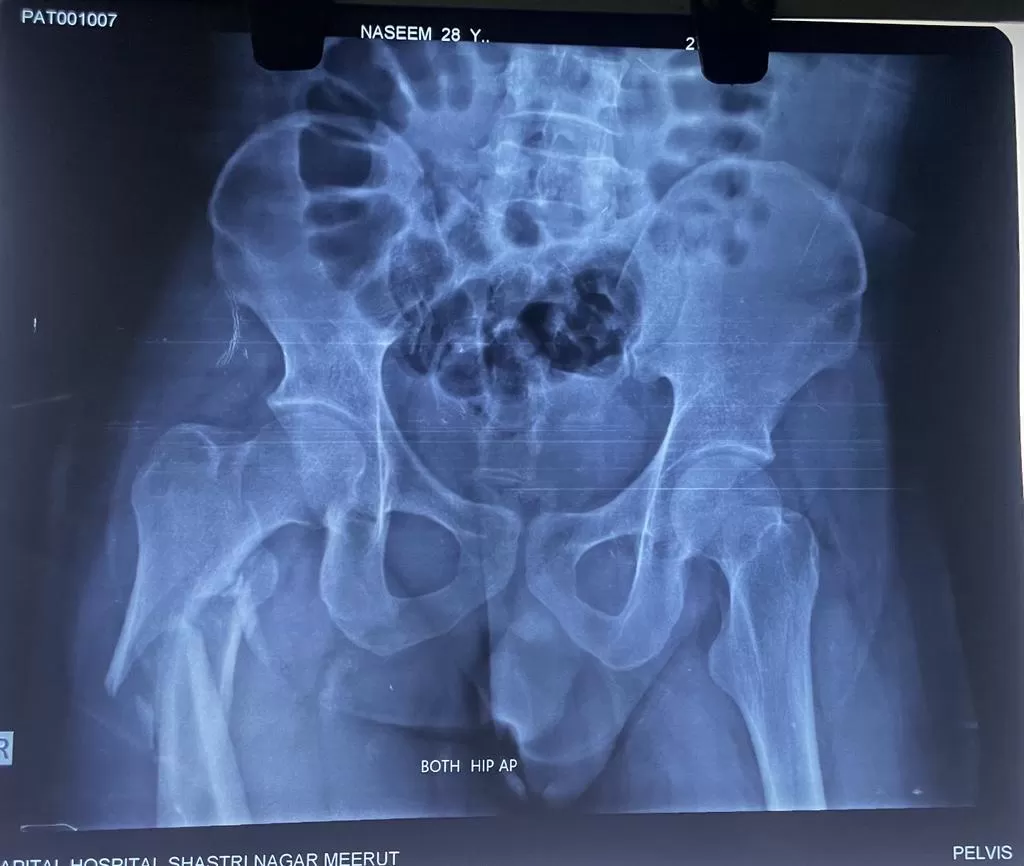

Mr. Naseem

Name: Mr. Naseem

Date of Operation: 8 Jan 2024

Age: 28 Years